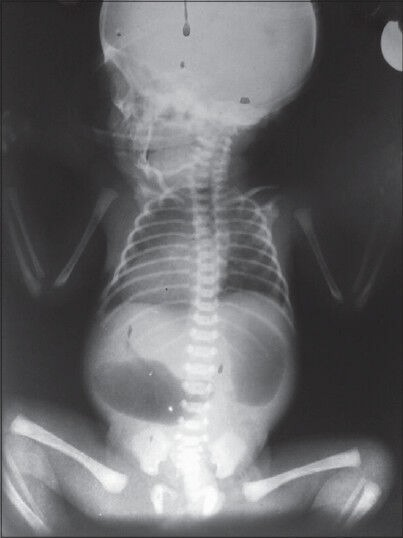

Puzzle 38

What's the Diagnosis?